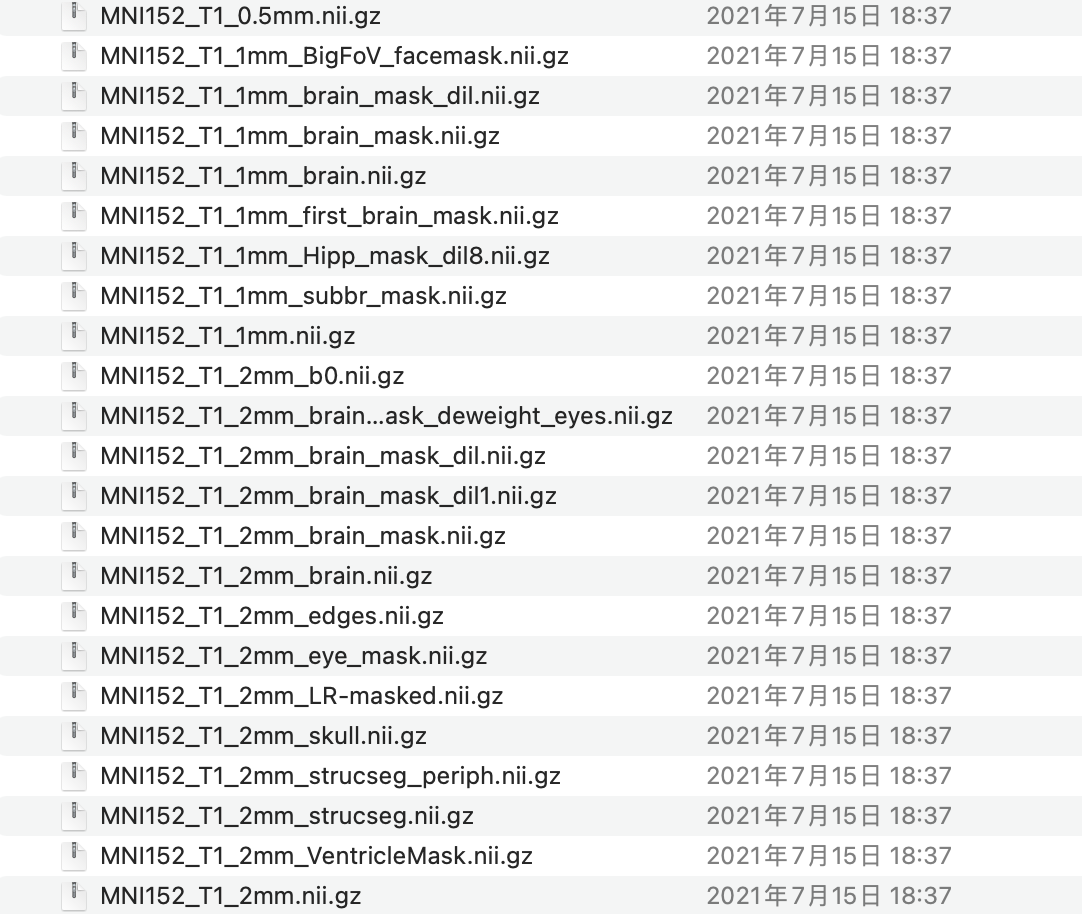

每个空间又可以有不同的分辨率,比如标准空间模板MNI152,就有1mm,2mm,0.5mm的分辨率。

常用的标准空间(MNI152)模板在/usr/local/fsl/data/standard下,方便使用。

提供了各种分辨率,各种需求的模板。我们可以将自己的数据配准到标准空间上,作为预处理的一部分。

最好的方法就是把他们配到同一个标准空间(如 MNI152)

配准方法同上面代码一样,只是把参考图像改为MNI152对应的分辨率(PS:官方只提供了3种分辨率,0.5mm, 1mm and 2mm).假设想要5mm的分辨率,那就把标准空间重采样到5mm(使用resample), 再配准。

flirt -in brats.nii.gz -ref MNI152_1mm_brain.nii.gz -out register.nii.gz -dof 12 -cost corratio

注意:MNI152_1mm_brain.nii.gz需要给对这个图像的地址(一般在/usr/local/fsl/data/standard),可以把他从原始库中拷贝到当前文件夹